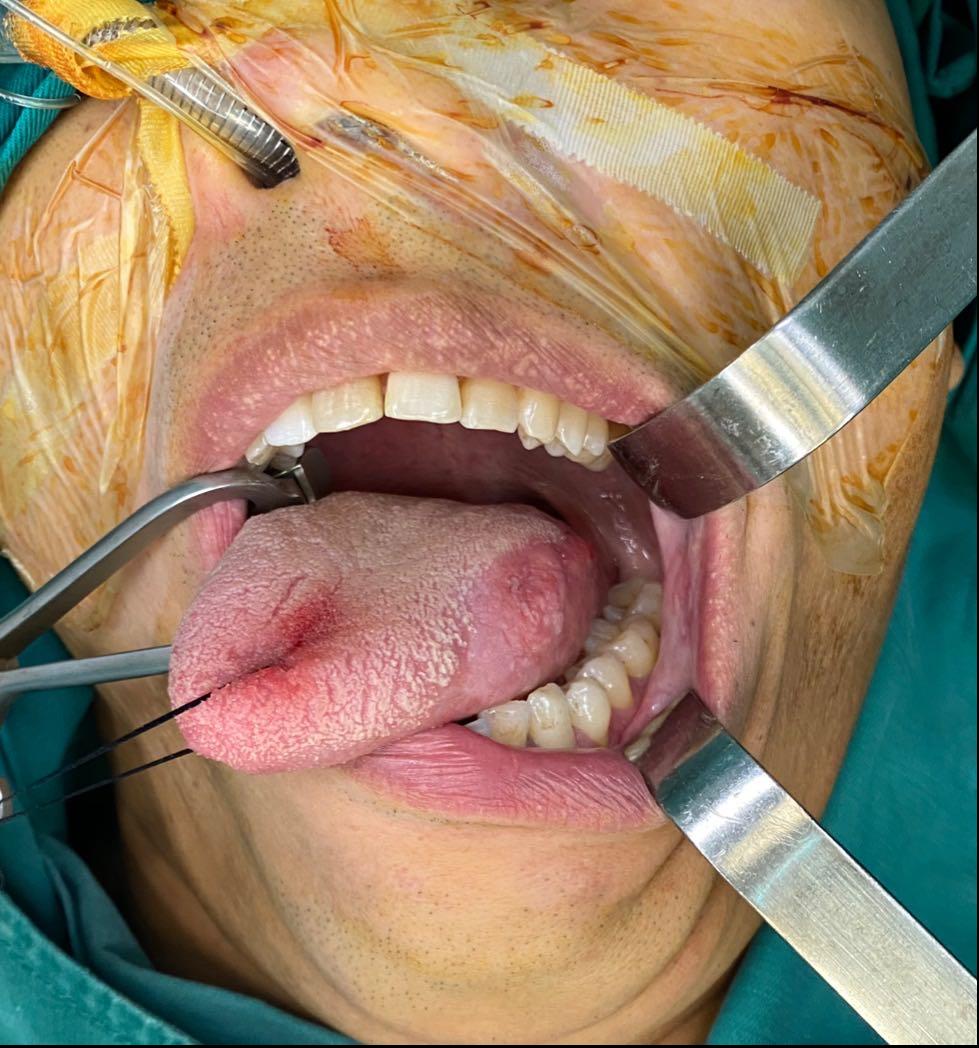

考虑到患者还年轻,为了提高患者术后生活质量,尽可能保留口腔功能,龙华区人民医院口腔外科闫征斌主任决定为他进行舌肿物扩大切除+功能性颈淋巴结清扫,保留患者的胸锁乳突肌、颈内静脉和副神经。

最终,手术非常成功,淋巴结未转移,一周左右患者就恢复了言语功能、吞咽功能,术后如期出院,张先生一家对手术非常满意。